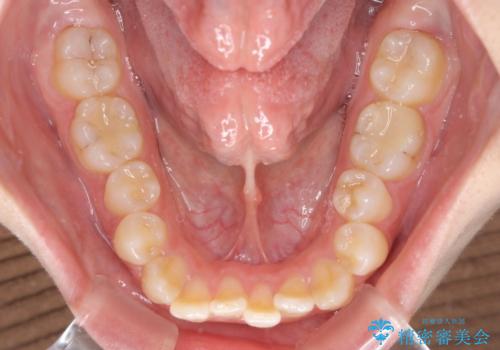

【モニター】オープンバイトをインビザラインで矯正治療

- 前歯の上下スペースによる食べにくさを気にして来院された患者様です。

インビザラインにより上下の前歯の隙間を閉じていくこととしました。

前歯のデコボコの解消と並行して上下の奥歯を圧下させるようにすることで、前歯を接触させるように計画しました。

上下の隙間に舌が入り込むことがオープンバイトの原因であったため、舌の筋肉のトレーニングも並行して行い、後戻りの抑制を図りました。